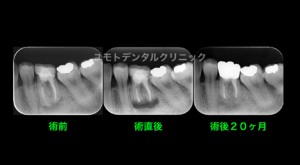

下の3枚のレントゲンは右下6番をそれぞれ照射角度を変えて撮影を行ったものになります。

(当時 正方線、偏近心撮影を行い、ポスト部周囲に疑問を感じ偏遠心撮影を加えて行っています。)

分岐部の透過像が初めて確認されたこと、既存のポストを3次元的に確認することができました。

ポスト周囲にはパーフォレーションなどはありませんでしたが、遠心根管内側にストリップパーフォレーション部があり、パーフォレーションリペアを行っております。

短期予後にはなりますが、予後観察時に症状の再発もなく分岐部の透過像の縮小傾向も確認できました。